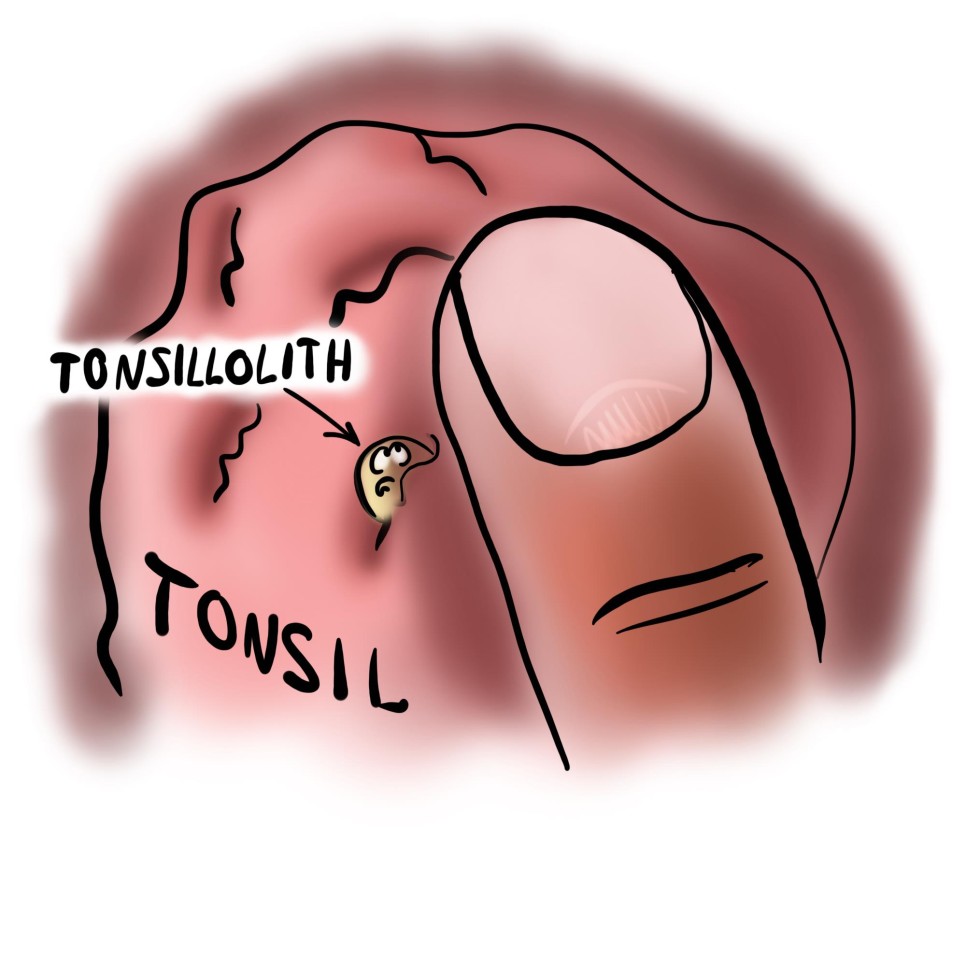

그렇게 많은 결석은 모두 어디로 갔을까요? 그리고 어디서 나타날까요?사실 눈에 보이는 결석만이 전부는 아닙니다.사실 눈에 보이는 결석만이 전부는 아닙니다. 결석은 편도의 더 깊은 곳에도 있습니다. 또한 편도의 최심부인 편도 중앙에서도 편도 결석이 자랍니다. 결석 제거를 위한 부분적인 편도절제술로 재발이 많은 이유가 그 때문입니다. 바깥쪽 편도 봉투를 자른 곳에서 안쪽에서 다시 바로 나옵니다.

편도결석이 주로 발병하는 위치에 따라 어떤 분들은 AgNO3라는 화학약품을 한 번 바름으로써 평생 재발하지 않는 경우도 있고 90%의 편도를 절제해도 한 달 만에 재발하는 경우도 있습니다.

편도결석이란? 편도결석은 건락성(cheesy)이 하얗거나 노란색 1cm 이내의 물질로 나타나며 구취(halitosis)와 인후통, 목물감 등을 동반하기도 합니다.

편도결석(tonsil loliths)은 편도라는 편도점막 공간 내에 상피조직의 찌꺼기가 축적되어 발생합니다. 편도염이 있으면 결석한다고도 알려져 있지만, 사실 편도염과는 관계없이 언제든지 일어날 수 있습니다. 구강위생이 불량하거나 비염부비동염으로 인한 후비루가 있는 경우에도 더 발생하기 쉽습니다.OPERATION 수술